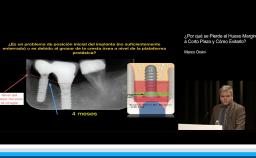

Se discuten aspectos fundamentales de los tejidos duros y blandos para obtener resultados predecibles en los casos de instalación inmediata de implantes en alvéolos post extracción (Tipo 1), centrándose en los riesgos y la necesidad de cuidadoso diagnóstico y plan de tratamiento.